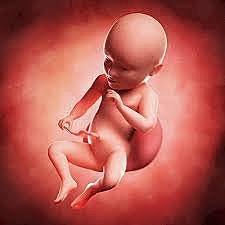

• Semana 32

47

Semana 32

Su cabeza está proporcionada con respecto al resto del cuerpo.

Las uñas han completado su desarrollo y si es un chico sus testículos ya se encuentran dentro de la bolsa escrotal.